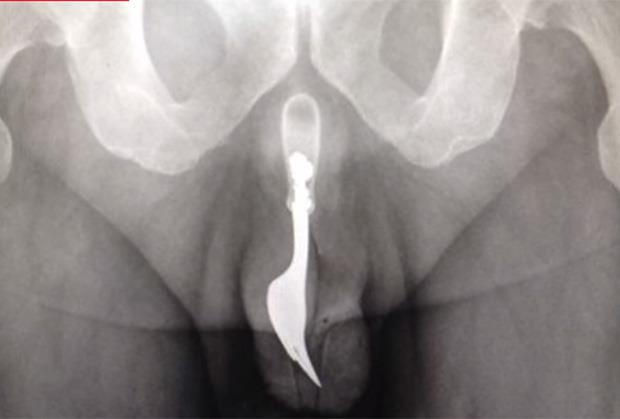

(VIDEO) BIZARNI SEKS: Vibrator zaglavila u bešici!